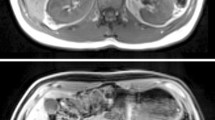

Segmentation of the entire kidneys and differentiation of their internal structures were performed in 12 healthy volunteers based on non-contrast-enhanced T1- and T2-weighted MR images. Two data sets (each acquired in one breath-hold) were co-registered using a rigid registration algorithm compensating for possible breathing-related displacements. An automatic algorithm based on thresholding and shape detection segmented the kidneys into their compartments and was compared to a manual labeling procedure.